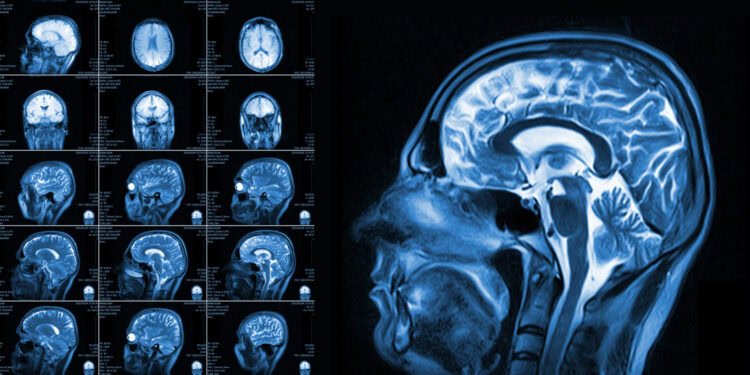

To observe brain function, the researchers utilized two advanced imaging technologies simultaneously. Participants entered a functional magnetic resonance imaging (fMRI) scanner. This machine measures brain activity by tracking changes in blood oxygen levels. At the same time, participants wore caps to record electroencephalography (EEG) data. EEG measures the electrical activity of the brain with high time precision.